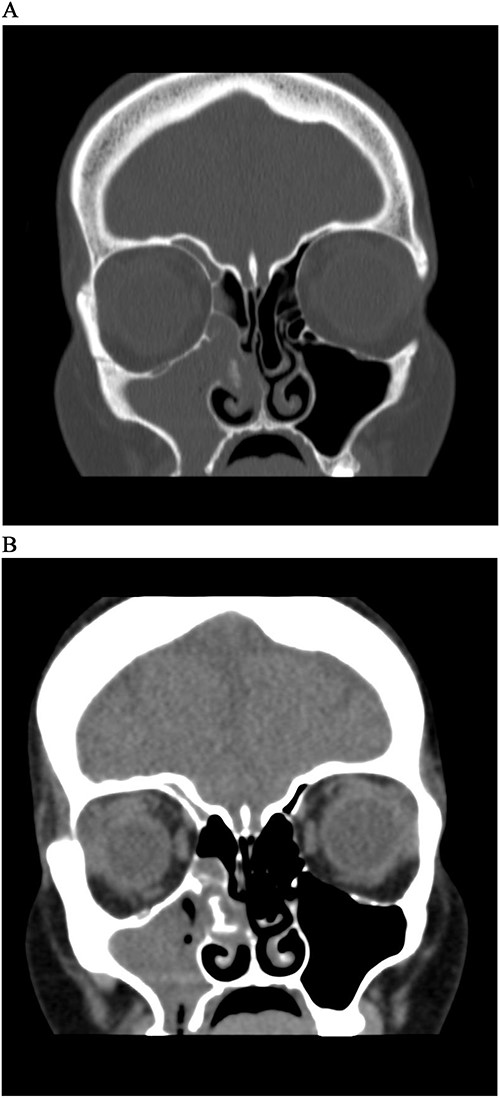

A 41-year-old woman presented to the ENT clinic in January 2020 with right clear to yellowish rhinorrhea. The nasal discharge started 2 months after her cesarean section delivery. On physical examination, nose vestibulitis was noted for that she was treated with antibiotics (Augmentin) for 1 week that significantly improved her symptoms. However, the patient presented 5 months later with 2 weeks history of brownish-to-greenish nasal discharge, in which she was treated again with Augmentin, along with nasal hypertonic saline and mometasone furate sprays. Rhinosinusitis and CSF rhinorrhea were suspected, and a computed tomography (CT) was done. Upon reviewing the CT, it showed complete opacification of the right maxillary and right ethmoidal sinuses with calcifications in the ethmoidal sinus with right ostiomeatal complex obstruction, and mild mucosal thickening at the right frontal sinus with no significant bone lesion (Fig. 1A). The left side sinuses were unremarkable while there was mild nasal septal deviation to the right. She was booked for functional endoscopic sinus surgery (FESS) + septo-turbinoplasty (STP), however, it was postponed due to COVID lock down. The patient was referred to the dental department for root canal therapy.

CT Sinus, bone window (A) and soft tissue window (B), coronal cut, shows complete opacification of right maxillary sinus and anterior ethmoidal cells, with a soft tissue mass extending from MM to septum with hyperdensity lesion.

Actinomycosis is an uncommon chronic bacterial disease that infects patients with risk factors such as dental operations, diabetes, immunosuppression, poor dental hygiene [1]. Actinomyces infection presents differently based on the site where the infection occurs. Common forms include orocervicofacial abscesses for patients with bad oral hygiene and dental issues, chest infections due to aspiration of gastric content, infections in the abdomen after surgery or gastrointestinal damage and infections in the pelvic area for those with intrauterine contraceptive devices [5–7]. Cervicofacial actinomycosis, which accounts for ⁓50% of all recorded cases, is the most common type of actinomycosis, followed by abdominal and thoracic actinomycosis (15–20%) [2, 8]. Although it’s very rare for actinomyces to infect the sinuses, a few cases were reported [9–13]. Jason E. Cohn et al. reported a case of unilateral maxillary sinus actinomycosis with a closed oroantral fistula 2 weeks after the patient had upper molar extraction. The patient presented with right facial pain, tenderness, as well as right ear fullness, pressure and hearing loss. A CT scan of the sinuses showed that the right maxillary sinus was completely opacified [9]. However, in our case the patient only presented with recurrent rhinorrhea and had complete opacification of both the right maxillary and ethmoidal sinuses (Fig. 1). Another study done in Korea analyzed the medical records of six patients with actinomycosis of the paranasal sinus in which all lesions affected the maxillary sinus unilaterally [10]. Similar to our case, a patient in Brazil suffering from chronic sinusitis was unresponsive to medical therapy due to the presence of actinomyces [11]. The present case report demonstrates analogous CT scan characteristics between fungal and Actinomyces infections which is consistent with the existing literature [12, 14]. While only the maxillary and ethmoidal sinuses were affected in our case, invasive actinomyces in another patient resulted significant damage to the maxilla, nasal bones and all three sinuses (maxillary, frontal and ethmoidal) [13].